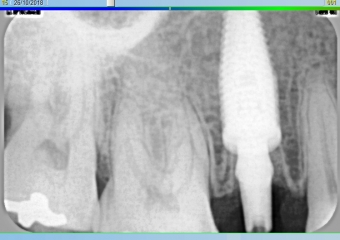

Rx Imediato

Rx final com dente definitivo